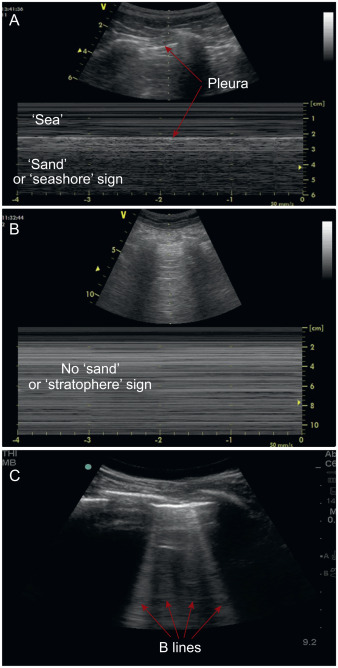

🖼️ The “seashore sign” vs “stratosphere sign” and B-lines can help distinguish: • pneumothorax • interstitial syndromes (pulmonary oedema, pneumonitis, fibrosis) POCUS becomes a bedside game-changer for pregnant patients with dyspnoea. 🔍🫁 Read more: https://t.co/mxQP57qVCQ